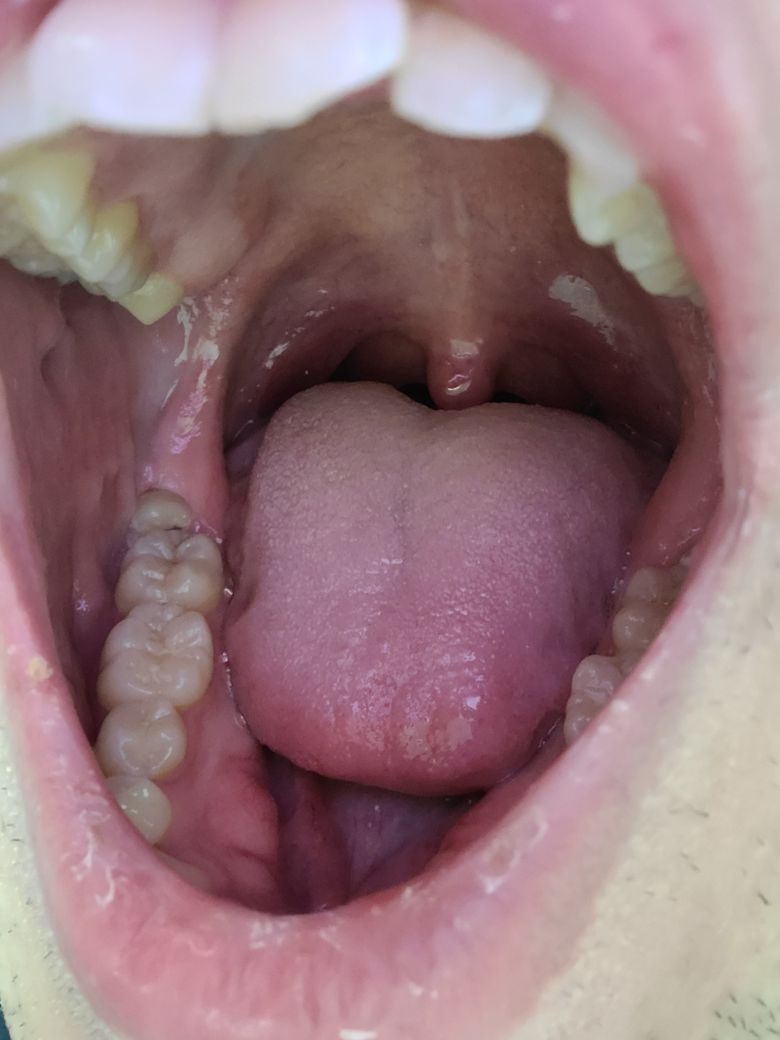

사랑니 충치인지 어금니 충치인지 질문입니다

몇일전에 밥먹다가 우득소리가 나고 약 3~4일 욱씬거리고 물마시면 매우 시린 증상 있었습니다. 카메라로 보니까 충치가 보이는거 같은데 사랑니쪽 충치인가요 어금니쪽 충치인가요?

그리고 충치는 심한상태일까요?

그리고 사랑니는 가끔씩 아픈적 있긴했지만 우득소리가 나느건 처음이라 혹시 치아가 깨졌을 가능성도 있을까요

• 1번 째 사진

사랑니에도 그리고 앞쪽 어금니에도 충치가 보입니다. 정확한 것은 x-ray 등을 찍어봐야 알 수 있을 것으로 보이며 임상 검사로 인하여 해당 부위도 긁어보아야 합니다. 또한 치아가 파절되었을 수도 있으므로 통증 및 불편감이 크다면 가까운 치과 방문 후 평가를 받아보시길 바랍니다.

지금처럼 나있는 사랑니는 무조건 빼시는 것이 좋습니다. 치과에 내원하여 빼시고 앞의 치아와 사이에 충치가 있을 가능성도 있어보입니다.

사진상으로 보면 아래 쪽에 부분매복 사랑니가 잇으신거 같습니다. 정확한건 치과에 가셔서 직접 검진을 받아보시고 엑스레이 사진을 찍어보시는게 좋을것같습니다.